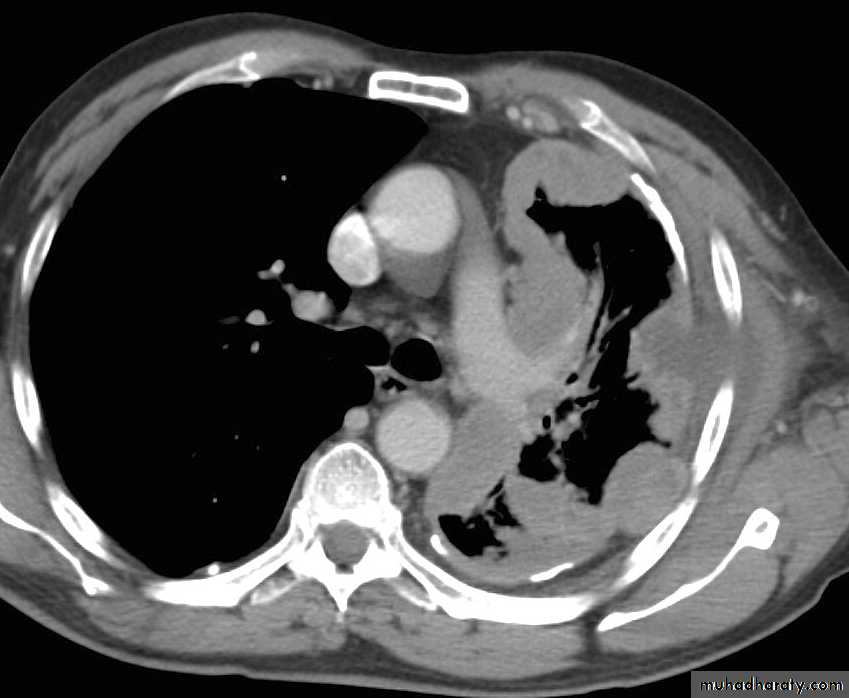

CT scan

BronchoscopyPneumothorax